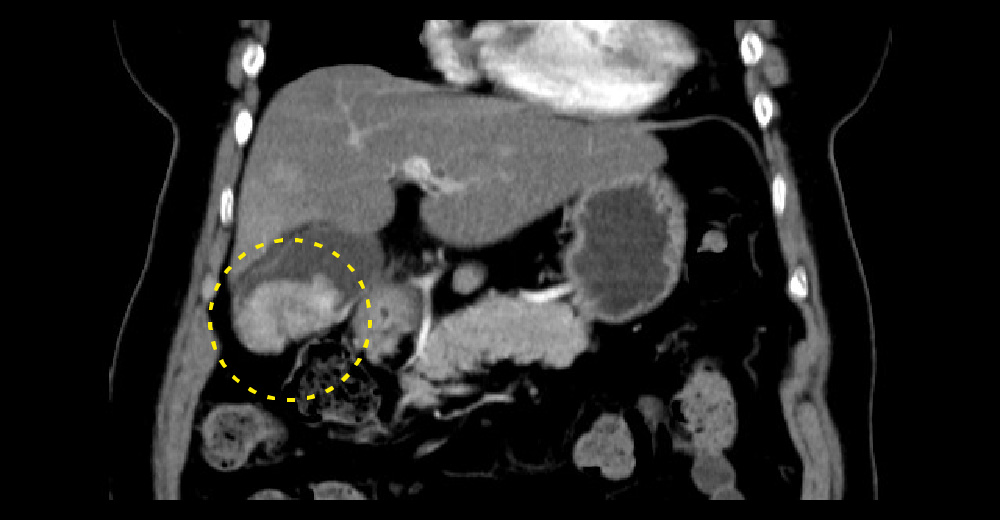

造影CT門脈相*冠状断